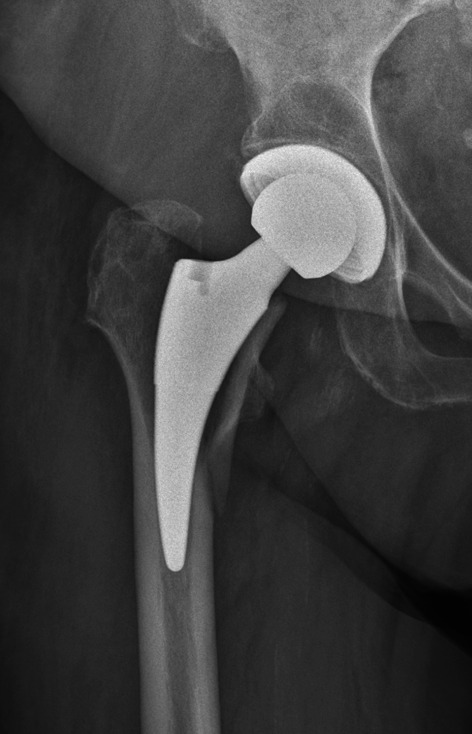

背景:骨盆和股骨形态与无骨水泥全髋关节置换术(THA)中早期股骨假体周围骨折(PFF)的发生有关。不同的手术方法和植入的骨干设计存在差异。因此,本研究分析了通过微创(MIS)前外侧入路进行无骨水泥短柄全髋关节置换术的骨盆和股骨形态:方法: 对1826例短柄THA进行了一项回顾性、单中心、多外科医生、倾向分数匹配比较研究。共有 39 名在术后 90 天内发生 PFF 的患者与非骨折患者按 2:1 的比例进行了匹配。股骨近端形态的分析包括股骨管外翻指数(CFI)、股骨管-髋臼比率(CCR)、股骨管-骨比率(CBR)、形态皮质指数(MCI)和股骨皮质指数(CI)。骨盆形态通过髂骨-髂骨比(IR)、髂前上棘到大转子尖的距离(AGT)进行分析。通过非参数检验和单变量回归分析,对两组患者的股骨和骨盆形态的多个参数进行了分析:结果:骨折组的 AGT 明显更高(104.5 mm ± 18 对 97.4 mm ± 9.8;P = 0.016)。所有其他股骨和骨盆参数在两组之间没有差异,同样也是根据PFF的温哥华类型进行比较:结论:与匹配的非骨折组相比,通过前外侧入路进行无骨水泥短柄THA的PFF患者的股骨近端和骨盆形态在多个放射学参数上没有差异。这些研究结果与其他采用不同骨干类型和方法的研究结果存在争议。今后的研究应重点分析骨盆几何形状和股骨近端形状对采用相同骨干类型的不同方法发生PFF的影响,反之亦然。证据级别 III级病例对照研究。

Background: The pelvic and femoral morphology are associated with the occurrence of early periprosthetic femoral fractures (PFFs) in cementless total hip arthroplasty (THA). Differences exist depending on the performed approach and implanted stem design. Therefore, this study was conducted to analyze the pelvic and femoral morphology in cementless short stem THA via a minimally-invasive (MIS) anterolateral approach.